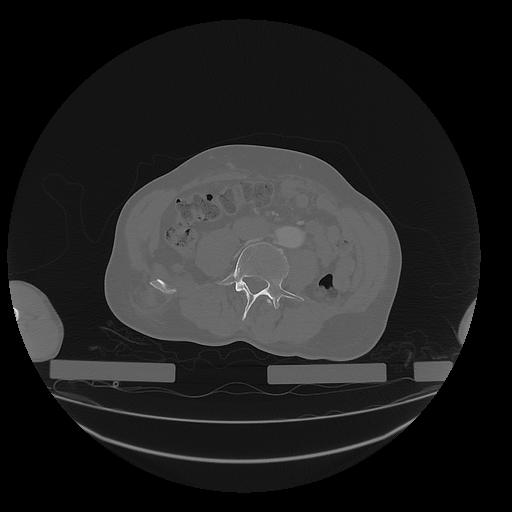

31 PULMON,CE,Vol,1.0,PULMON,,